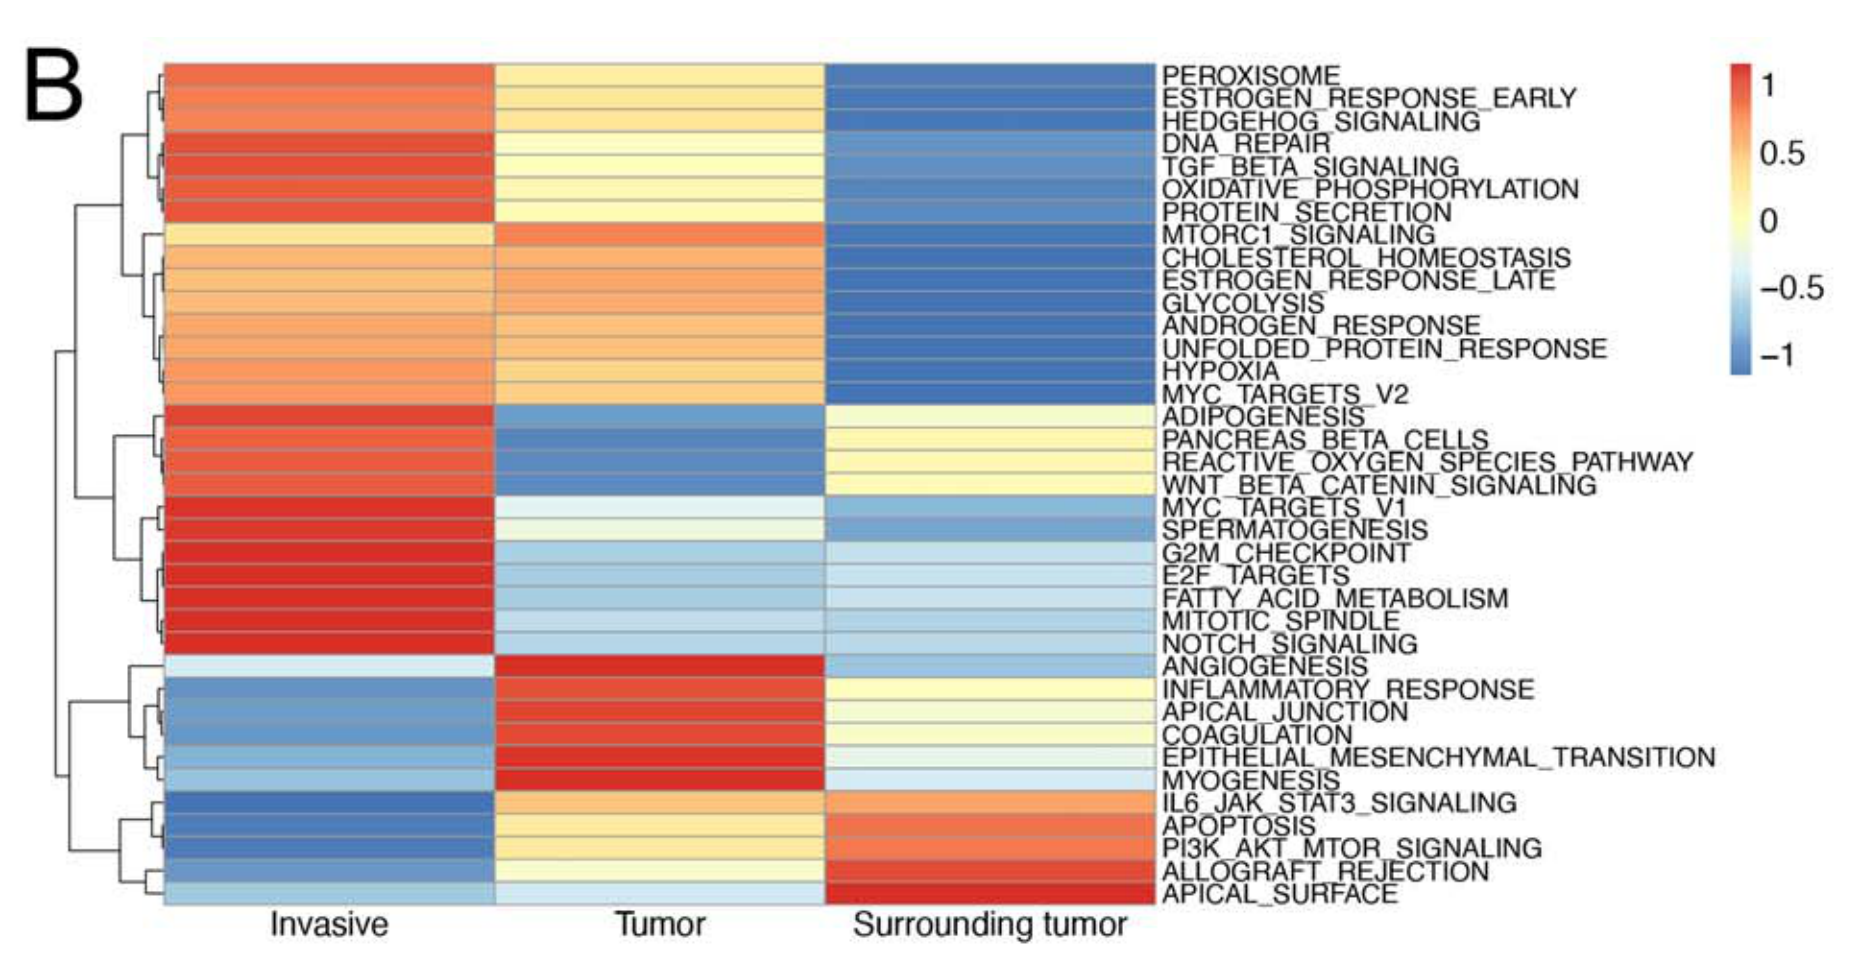

Sun D. et al. - 2022

STRIDE: Accurately decomposing and integrating spatial transcriptomics using single-cell RNA sequencing

Condition Dimension

N/A

Data Components

Biological AnnotationGene Expression Matrix

Data

Modality

Sequencing-based: Deconvolved data

Resolution of observation

Multi-cellular

Visualized Elements

Statistic

How does the activity of specific biological pathways vary across spatially defined regions within a tissue?

Biological

Molecular

Abstraction

Complete

Chart Type

Heatmap

Communicative/Contextualization

None

Comparative Design

Explicit encoding

Layout

Linear

Scalability Strategy

Summay/Aggregate